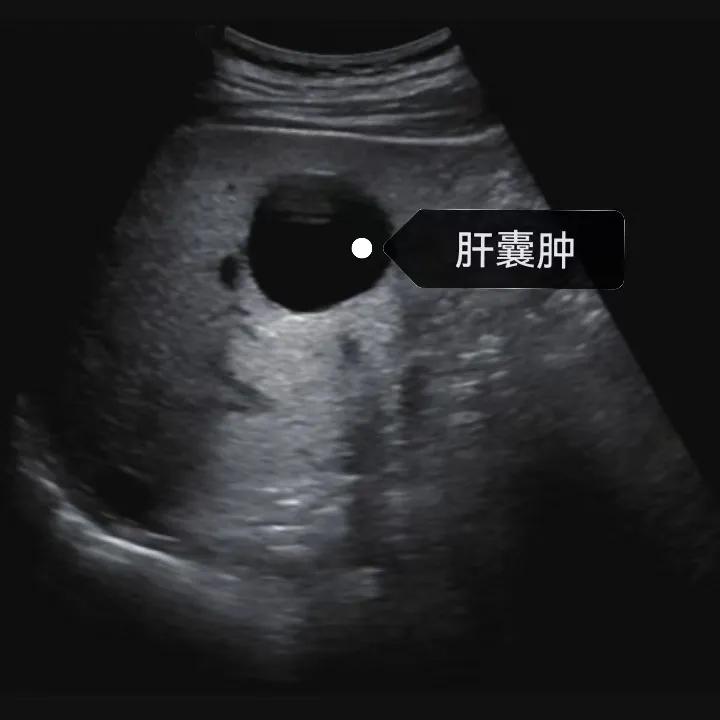

漯河市中醫院健康科普:認識肝囊腫

隨著人們健康意識的提升,越來越多的人每年會進行健康體檢,由于腹部(肝膽胰脾)超聲作為常規體檢項目之一, 肝囊腫的檢出率也愈發升高,大部分人對“腫”字都比較困惑,今天我們就來一起了解一下肝囊腫。

肝囊腫是一種常見的肝臟良性疾病,呈圓形或橢圓形,外由上皮細胞包裹形成包膜,內由清亮、無色、無細胞成分的囊液填充,看上去就像是一顆注滿了水的氣球,因此通俗一點說就是肝臟中的“水泡”。

超聲通常是診斷肝囊腫的首選方法,彩超對肝囊腫的檢出率可達98%,<1cm的囊腫也可檢出。肝囊腫常表現為圓形或橢圓形無回聲,包膜光滑完整,邊界清晰,可有側壁回聲失落征象,后方回聲增強。病程長、囊腫較大者或囊內有過出血、感染者,無回聲腔內可見少量絮狀回聲漂浮。超聲對肝囊腫的診斷準確而靈敏,且方法簡單、無創、費用低、可重復性高,因此常常被作為首選。